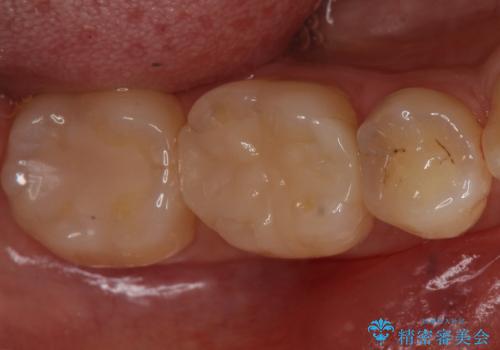

歯と歯の間の虫歯 セラミックインレーでの治療

- 矯正後の検査で歯と歯の間の虫歯が確認された患者様です。

虫歯の除去後、セラミックインレーで修復していきます。

レントゲン画像からは読み取りづらいですが、視診にて歯の一部が黒く透けているのが確認できました。

小さな虫歯でも見落とさずに精度の良い修復をすることで二次う蝕のリスクを減らすことができます。